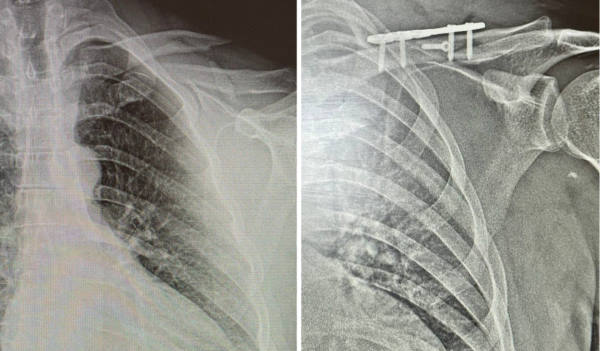

- Пациент был осмотрен травматологом и терапевтом, в экстренном порядке госпитализирован в травматологическое отделение с диагнозом «Закрытый оскольчатый перелом средней трети левой ключицы, со смещением отломков», сопутствующее алкогольное опьянение, - сообщили в БСМП.

Мужчине тут же провели оперативное вмешательство для сопоставления частей переломанной ключицы при помощи пластины с угловой стабильностью и винтами. Прогноз благоприятный, отмечают врачи.